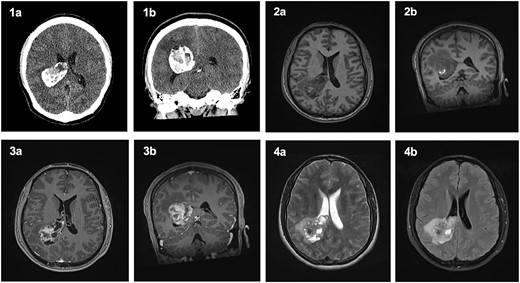

The patient was started on oral dexamethasone, resulting in the improvement of his headaches. The differential diagnosis based on imaging findings included an atypical meningioma, central neurocytoma, choroid plexus papilloma or carcinoma, ependymoma or an oligodendroglioma. He underwent a right parietal craniotomy with gross total resection of the lesion. Intraoperatively, use of the Vycor™ ViewSite Brain Access System (VBAS) was utilized, which allowed for optimized surgical site access, and reduced the risk of brain retractor injury to surrounding structures, namely the precentral gyrus. This was combined with intraoperative ultrasound (Fig. 3), which provided real time imaging and guided the extent of the resection. In addition, neuromonitoring and neuronavigation (Fig. 2) were incorporated to further reduce the risk of damage to surrounding structures. As part of the neuromonitoring, motor evoked potentials (MEPs) were performed to identify the precentral gyrus prior to insertion of the VBAS (Fig. 4), ensuring that any resection occurred posterior to the motor strip. During surgery, it was noted that the lesion was haemorrhagic and easily friable, with evidence of a previous recent haemorrhage.

Planned trajectory for excision of the tumour, as seen on the neuronavigation system.